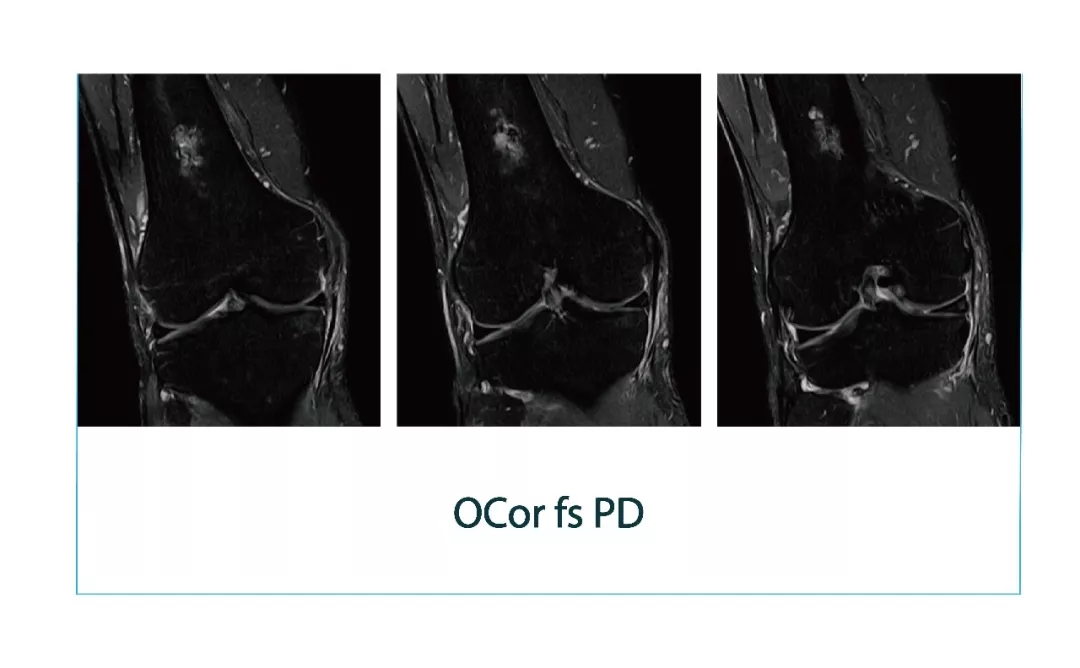

【朗润影像档案】磁共振影像病例分享(编号20180112)